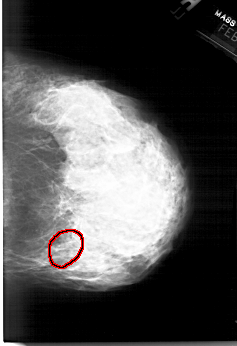

A_1564_1.RIGHT_CC

RIGHT_CC LINES 6226 PIXELS_PER_LINE 4261 BITS_PER_PIXEL 12 RESOLUTION 43.5 OVERLAY

FILE: A_1564_1.RIGHT_CC.OVERLAY

TOTAL_ABNORMALITIES 1

ABNORMALITY 1

LESION_TYPE CALCIFICATION TYPE PLEOMORPHIC DISTRIBUTION SEGMENTAL

ASSESSMENT 4

SUBTLETY 4

PATHOLOGY BENIGN

TOTAL_OUTLINES 1

BOUNDARY